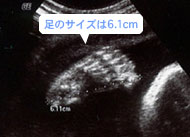

五本の足の指、骨もはっきり映っています。超音波では足の大きさも測れます。(妊娠30週)